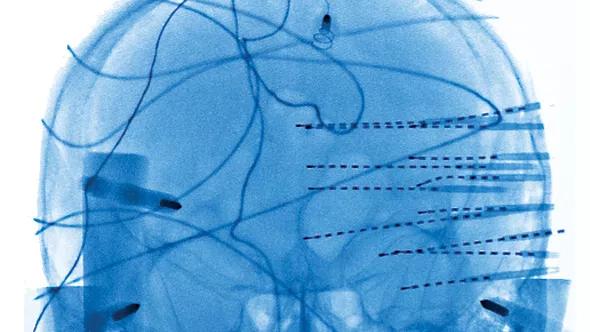

In these seizure disorder patients, many SEEG electrode contacts (as many as 200) are placed directly into the brain to define the area responsible for disease. This methodology has been pioneered in the United States by one of us (Dr. Gonzalez-Martinez) and uses advanced imaging methods in coordination with stereotactic techniques to precisely map the cortical areas responsible for generation and propagation of epileptic activity.

After formulating an individualized hypothesis about the epileptogenic zone’s location, physicians plan a tailored SEEG implantation strategy with the goal of confirming or rejecting the hypothesis. The precision of the stereotactic technique allows the desired targets to be reached and recorded from lateral, intermediate or deep structures in a three-dimensional arrangement, thus accounting for the dynamic, multidirectional spatiotemporal organization of the ictal discharges (Figure 1).

Figure 1. Patient in stereotactic frame with SEEG recording electrodes in place (left); three-dimensional model (right) shows brain region activation during phases of the card game. The 3-D image was constructed with Brainstorm Image reconstruction software. (See: Tadel F et al. Brainstorm: A User-friendly Application for MEG/EEG Analysis. Comput Intell Neurosci vol 2011; 2011:879716.)